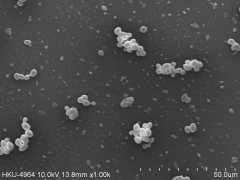

Magnification of the plastic surfaces (by scanning electron microscopy) confirmed that exposure to 3 µg/mL purpurin prevented the formation of biofilms and disrupted pre-formed biofilms. Furthermore, tentacle-like filaments (hyphae) that normally project out from C. albicans cells in biofilms were no longer present.

Filaments were also absent when cells were grown on a gel or in a liquid containing purpurin in addition to nutrients that would normally encourage filamentation.

The ability of C. albicans to grow in filament form and develop into biofilms on a plastic surface (left photo) is blocked by the addition of purpurin (right photo).